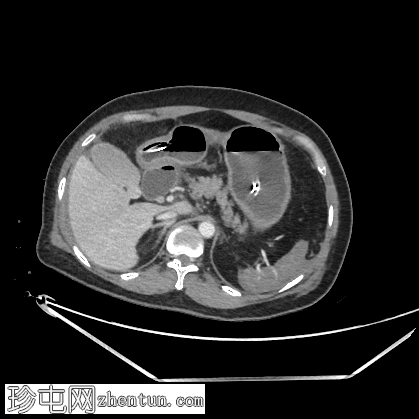

轴位

平扫

空肠(长段,60 cm)肠壁弥漫性节段性增厚。肠壁呈高密度影,平扫CT值约为56 HU,并可见强化。

可见肠系膜水肿和血管充血,以及少量腹水。

肠系膜上动脉和静脉通畅,未见血栓。

影像学表现最提示黏膜下出血。

鉴别诊断包括感染性肠炎。